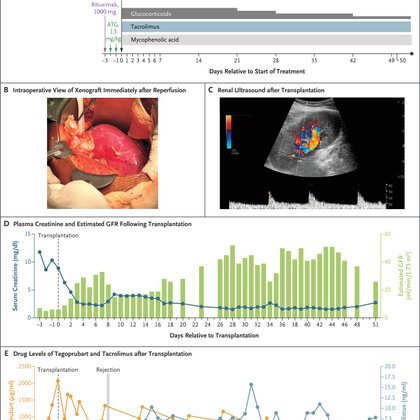

Presented at #ISNWCN: A new report describes the transplantation of a gene-edited porcine kidney in a hemodialysis-dependent man with long-standing diabetes, advanced vasculopathy, and marked dialysis-access challenges. Read the full report: https://t.co/itHbQDBPIu

🚨BREAKING: Our report on the first-ever pig kidney xenotransplant in a living human with ESRD is now published in @NEJM! A major milestone in transplantation, paving the way for a new era of organ replacement @mgh_transplant @MGHKidneys @eGenesisBio more:

Xenotransplantation offers a potential solution to the organ shortage crisis. A 62-year-old hemodialysis-dependent man with long-standing diabetes, advanced vasculopathy, and marked dialysis-access...